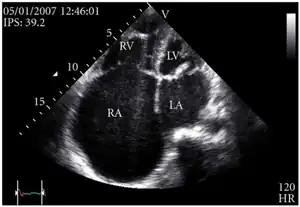

Echocardiogram: severe TR